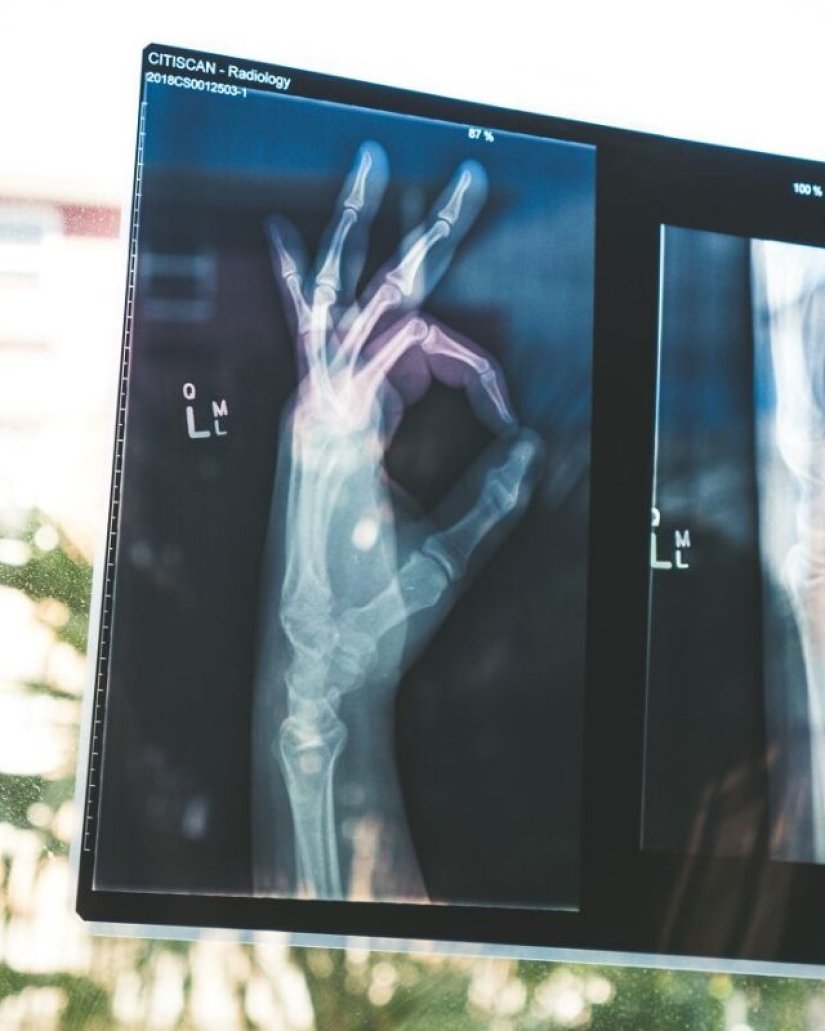

1. When x-ray technology first became widely available to pediatricians, they noticed an astounding number of broken bones. Puzzled doctors have suggested that this is the first time a previously unknown bone disease is being observed in children. It turns out we had no idea how common child abuse was.